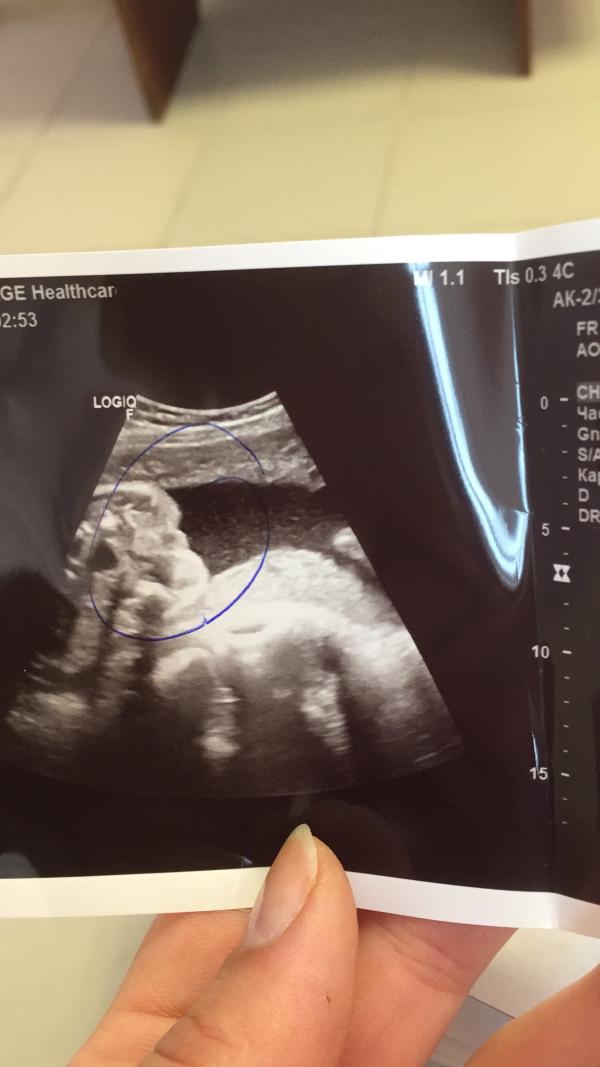

Всем привет, как думаете, это яички или половые губы?

Девочка) у пацана бы уже стручок был виден)))) я с сыном сразу увидела на 17 недели, а у дочи вот такие губы половые

Вот у нас похожая пипка! Я все глаза сломала всматриваться! Узист сказала 80% девочка, но все же 20% остаётся на мальчика 🤦♀️ хочется знать точно

Нам тоже узист говорит, для яичек маловаты и писюна не разглядела, но и на губы не похоже😀

Изменила фото, ноги поджаты к животу, вид сверху)

Ноги поджаты к животу получается, вид сверху. Изменила фото